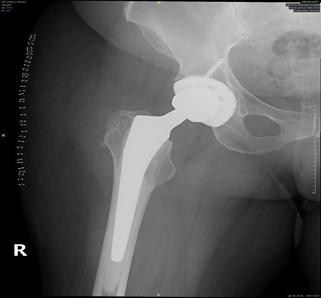

In primary total hip replacement of non-sicklers we usually rasp the femur before implanting the femoral component, in patients with sickle cell disease we did reaming the femur to avoid any femoral canal perforation. A guide wire was used to check the direction of our reaming and rasping in the femoral canal (Figure 3 & 4).

In some cases there is narrowing of femoral canal due to neocortex formation in the endosteum, so we used a straight narrow cylindrical shaped type of femoral stem. Image intensifier was used in these cases to detect any femoral perforation fracture or malposition of the femoral stem. Femoral fracture and/or acetabulum fracture have been reported in sickle cell anemia patients with THR.